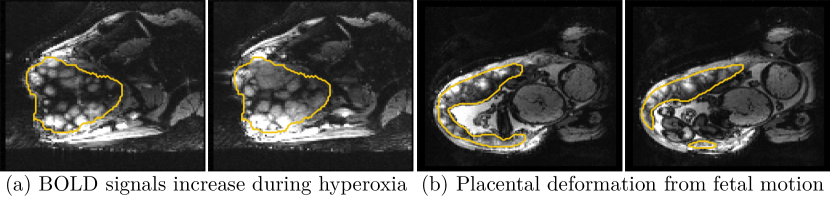

Despite its importance for many downstream clinical research tasks, placental segmentation is often performed manually and can take a significant amount of time, even for a trained expert. For BOLD MRI studies, manual segmentation is rendered more challenging due to the sheer number of MRI scans acquired and rapid signal changes due to the experimental design. Experiments acquire several hundred whole-uterus MRI scans to observe signal changes in three stages: i) normoxic (baseline), ii) hyperoxic, and iii) return to normoxic. During the hyperoxic stage, the BOLD signals increase rapidly, leading to hyperintensity throughout the placenta. Furthermore, the placental shape can undergo large deformation caused by maternal breathing, contractions, and fetal motion which can be particularly increased during hyperoxia [25]. See Fig. 1 for two examples.